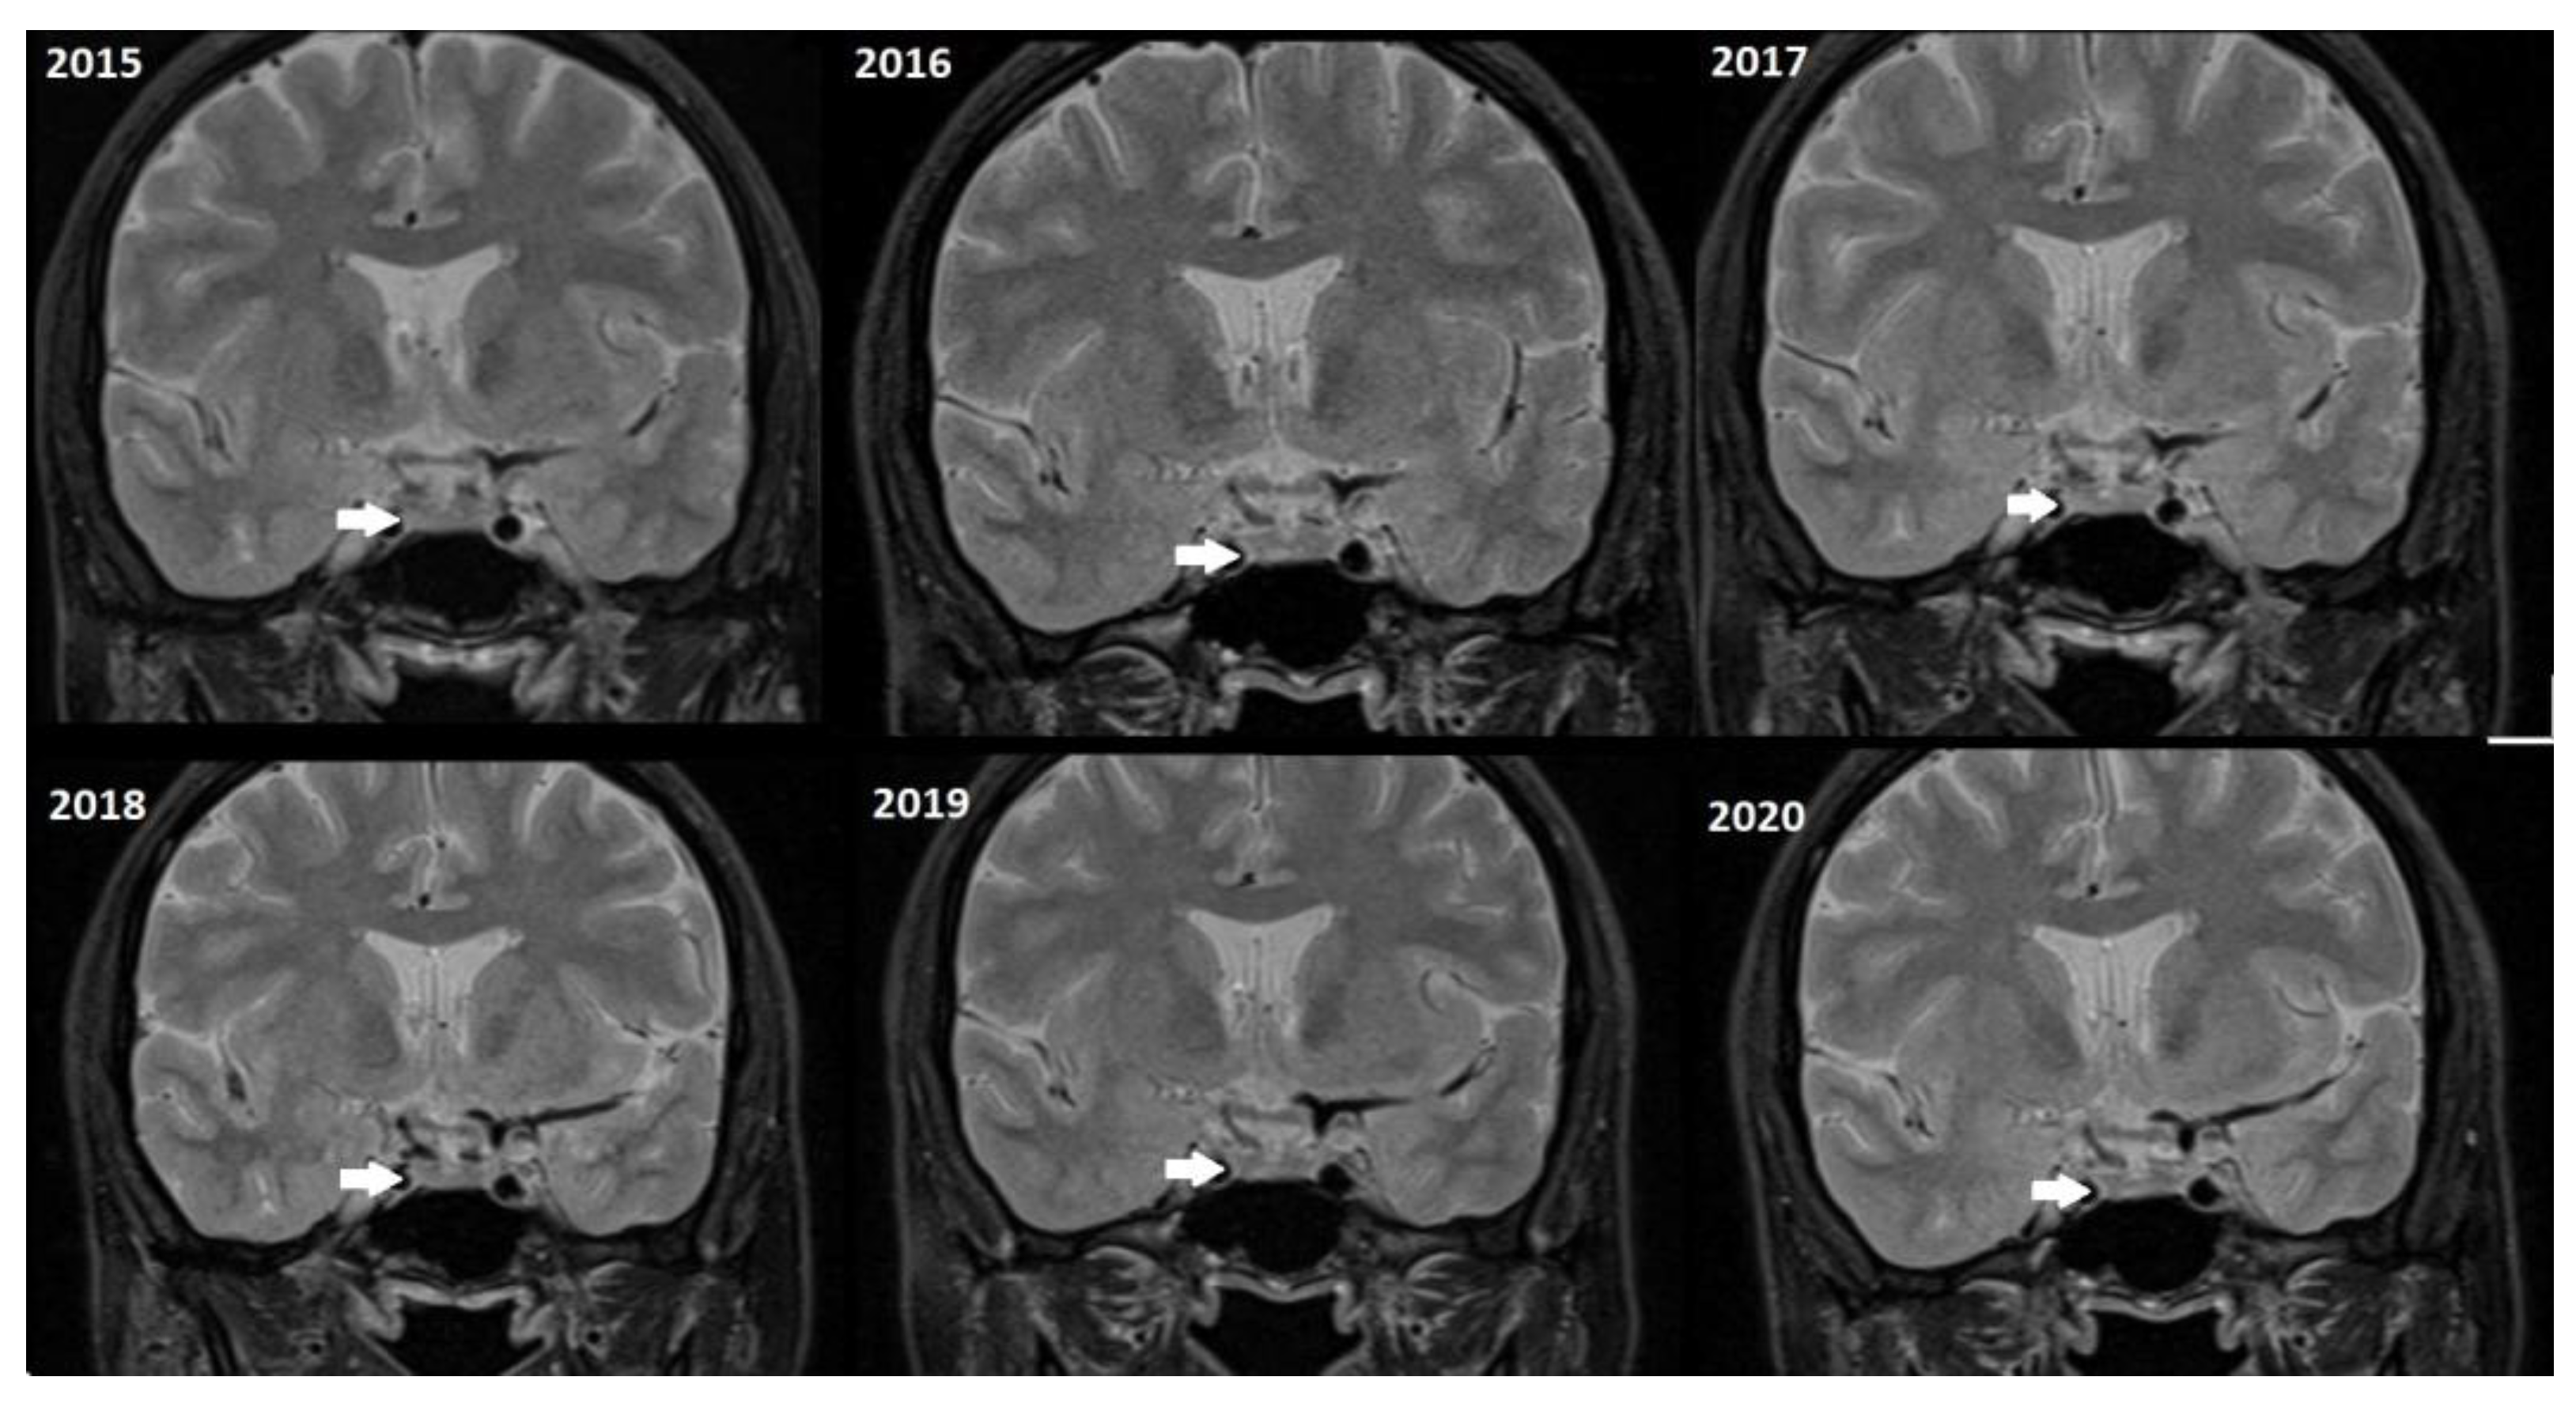

Although, the main cohort contained patients referred between 2020 and 2024, Figure 2, Figure 3 and Figure 4 shows a representative case with historical scans (2015–2020), retrieved from PACS, to demonstrate temporal stability. No evidence of recurrence of tumors in any of the nine who underwent resection of macroadenomas during this period was seen.

Figure 2.

Representative coronal images (2015–2020) of a stable microadenoma (arrows) of a 33 Y/O woman. The left upper image from 2015 is a delayed image, and the other six images are dynamic MRI follow-ups for this patient. In 2017, the patient had two follow-ups in the first and second half of the year. In the 5 years of follow-up, no size change can be seen.